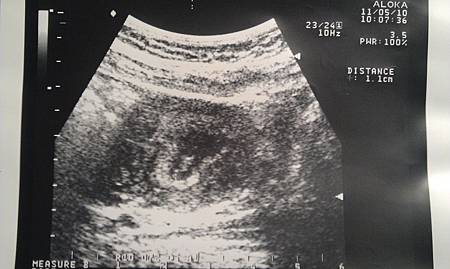

1.1cm 大約7W

醫生說喝水喝太少了,說那一坨黑黑的床不夠圓,

我看了半天,真的還是一坨...沒啥太大感覺耶....

不過!!!!!

今天聽到心跳了!

我只覺得滿意[ 很好,繼續好好長大吧! ]

到是準老杯,整個興奮不已啊!